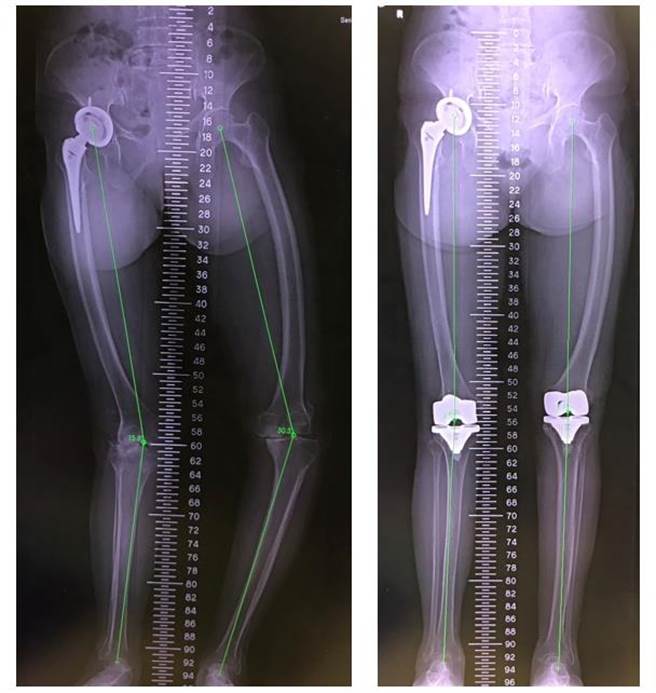

李阿嬤右膝關節的膝外翻變形大於15度且左膝關節的膝內翻變形大於30度(左圖),幸經微創膝關節置換手術成功恢復筆直雙腿,走路也不再歪斜、常跌倒(右圖)。(大里仁愛醫院/潘虹恩台中傳真)

由於李阿嬤右膝關節的膝外翻變形大於15度且左膝關節的膝內翻變形大於30度,手術難度高,幾位醫師看了X光後紛紛打退堂鼓,才輾轉到大里仁愛醫院。經過約2.5小時手術,李阿嬤術後當晚即可下床走動去上廁所,隔天開始復健運動。黃贊文回憶,阿嬤術後當晚下床走路一步一步練習、適應全新的膝關節,臉上驚喜又忐忑不安的表情令人印象深刻。